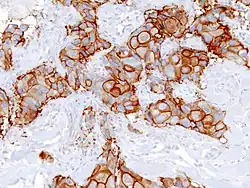

Invasive ductal carcinoma of the breast assayed with anti Mucin 1 antibody. -

Immunohistochemistry of breast cancer (Infiltrating ductal carcinoma of the breast) assayed with anti HER-2 (ErbB2) antibody. - Immunohistochemistry of invasive ductal carcinoma of the breast representing a scirrhous growth. Core needle biopsy. HER-2/neu oncoprotein expression by Ventana immunostaining system.